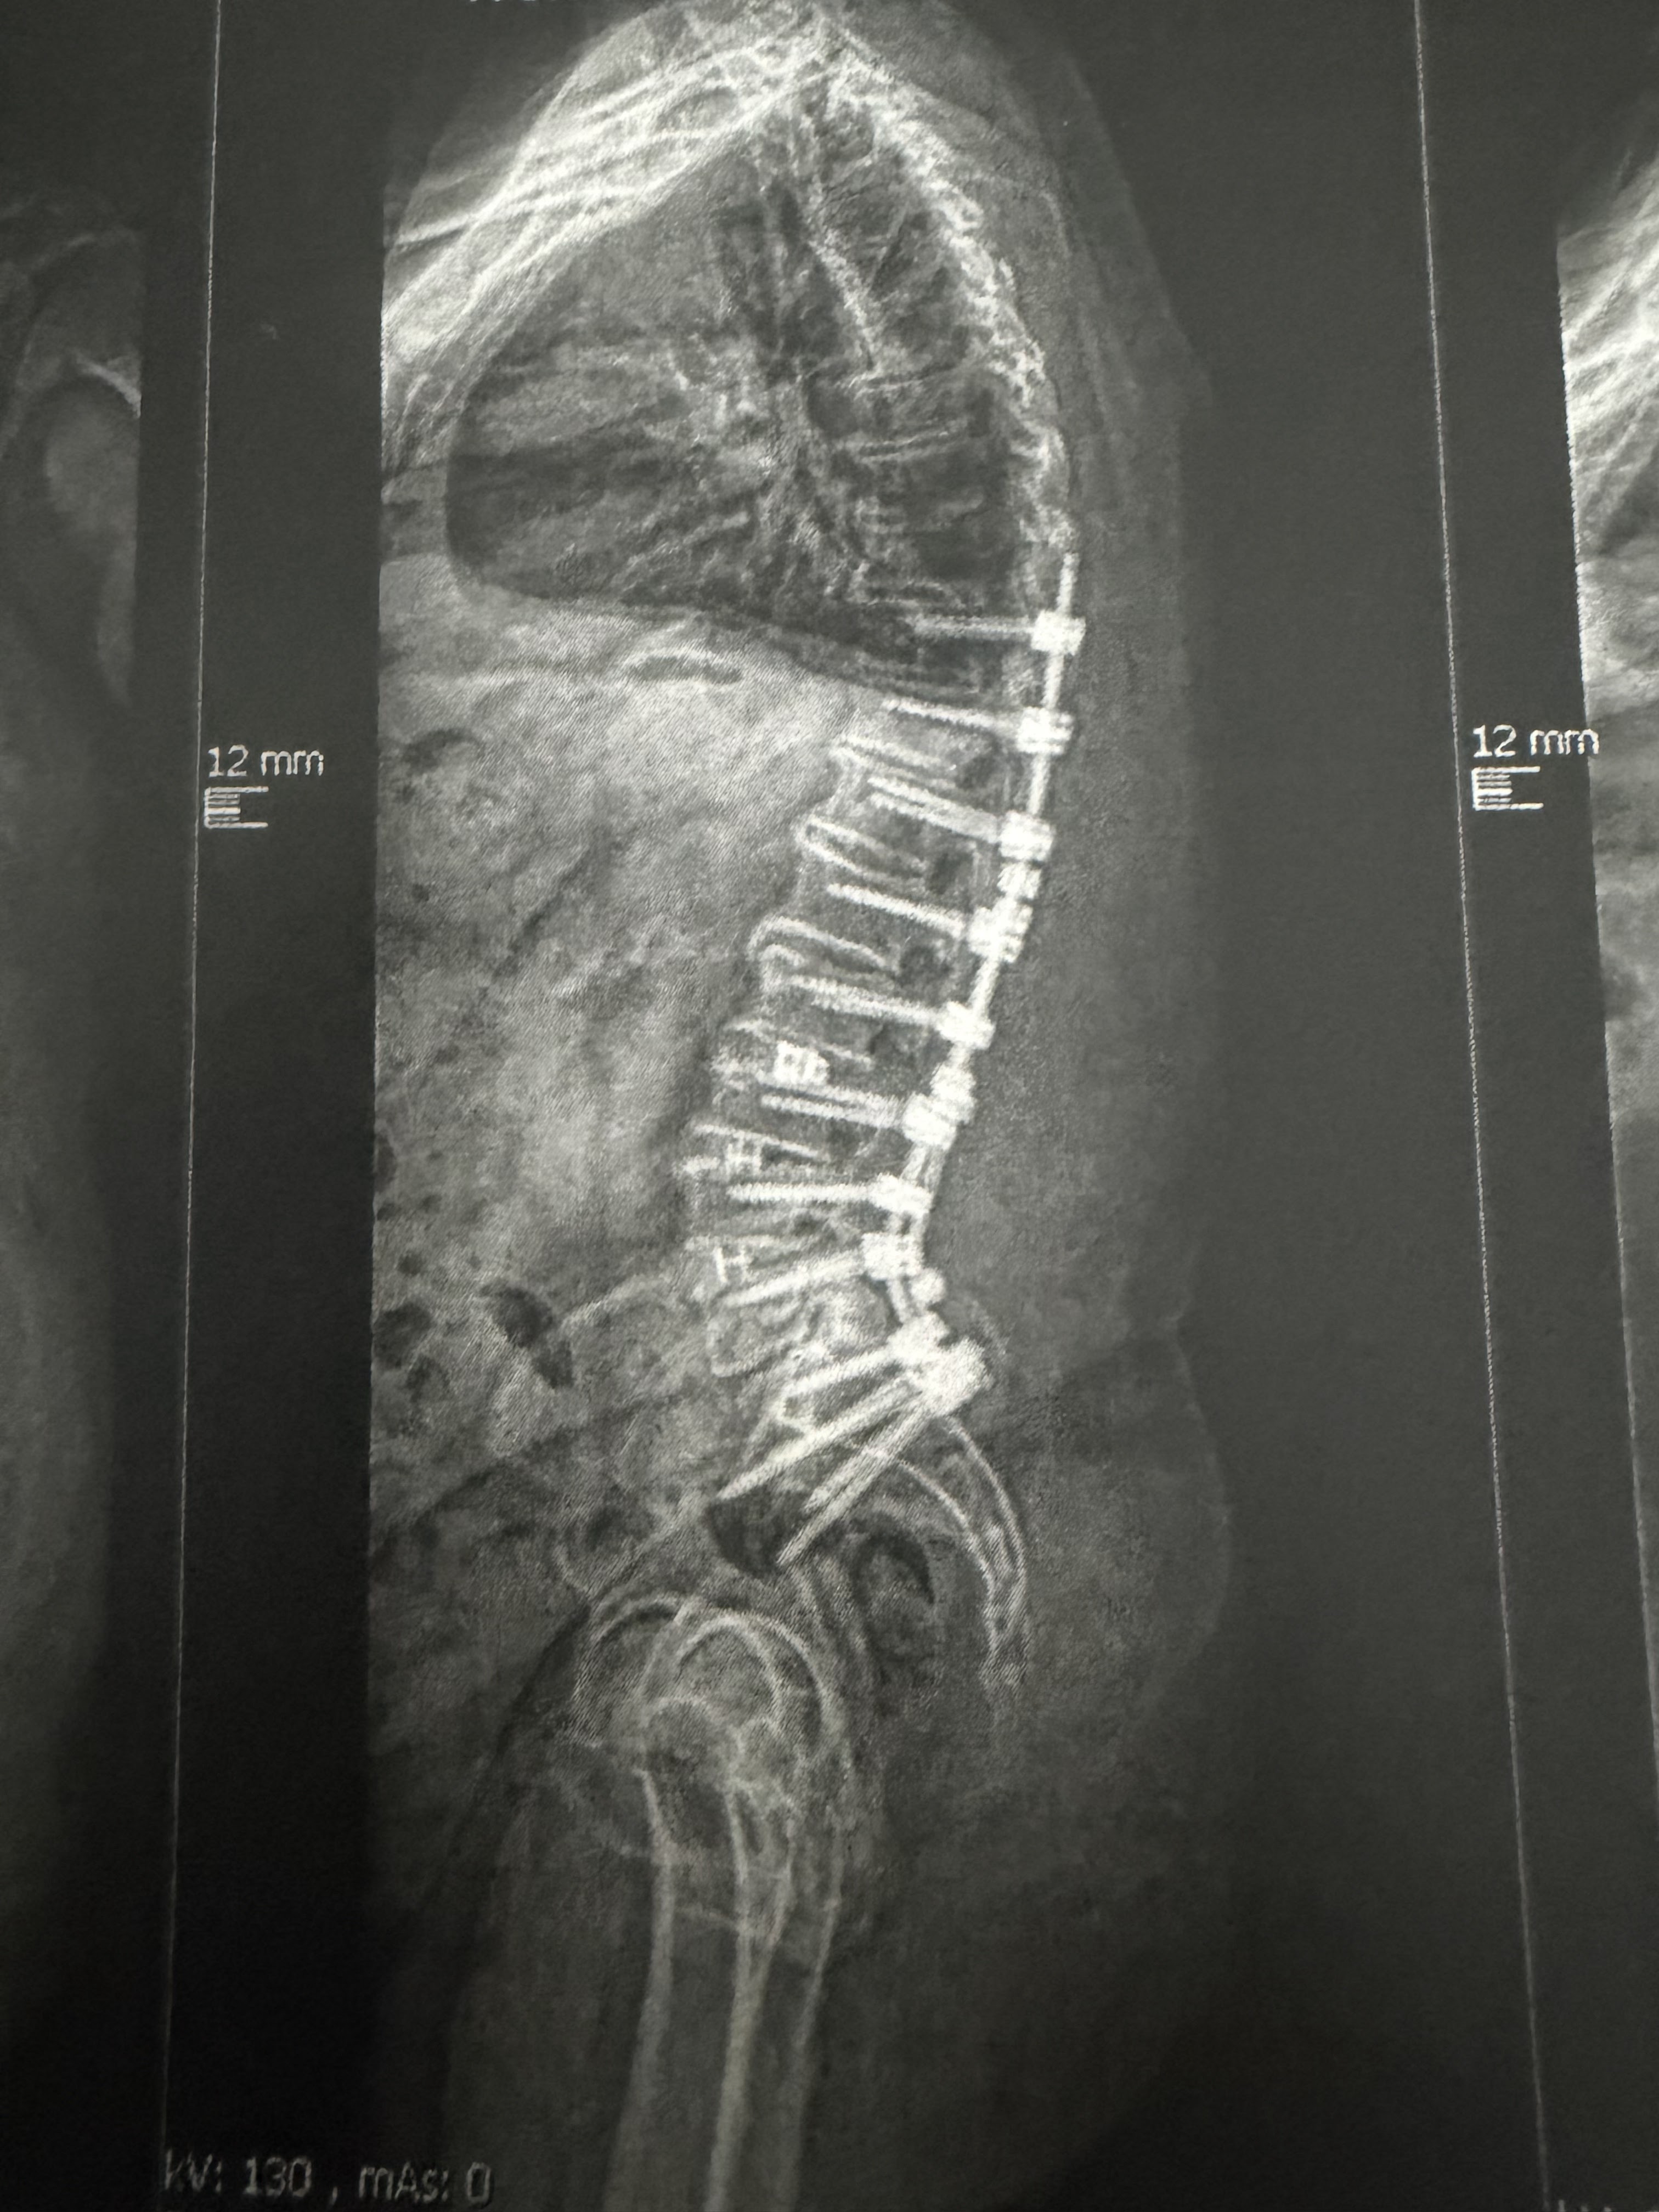

Und ich, Renee: Nach 40 Jahren harter Arbeit auf dem Bau musste auch ich meinen Körper aufgeben. Vier Rückenoperationen später und mit einer bleibenden Fusshebeschwäche schaffe ich kaum noch Wege ohne Rollstuhl. Mein Beruf, mein Stolz, mein Leben draussen – einfach weg.

Moi, Renee: après 40 ans de travail physique dans le bâtiment, mon corps a lâché. Après quatre opérations du dos et avec une faiblesse permanente du pied, je ne peux presque plus me déplacer sans fauteuil roulant. Mon métier, ma fierté, ma vie en plein air – tout a changé.